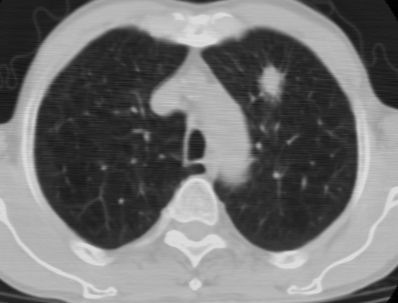

标题: CT24783:m71,既往肺心病史3年,现咳嗽,憋喘。 [打印本页]

标题: CT24783:m71,既往肺心病史3年,现咳嗽,憋喘。

1、左肺上叶spn,毛刺+分叶+血管集束征,考虑周围型肺癌可能性大

2、全小叶性肺气肿。

1)左肺上叶周围型肺癌可能。2)两肺全小叶型肺气肿。

左上周围型肺癌,全小叶型肺气肿。